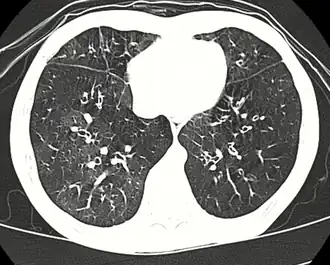

| TAC de alta resolução onde se observa bronquiolite obliterante | |

Entre as causas estão a inalação de partículas tóxicas, infeções respiratórias, doenças dos tecidos conjuntivos ou na sequência de um transplante de medula óssea ou de coração ou pulmões. Os sintomas podem só ocorrer passado duas a oito semanas da infeção ou da exposição à substância tóxica. O mecanismo subjacente consiste numa inflamação que provoca a formação de tecido de cicatrização. O diagnóstico é realizado com TAC, exames à função dos pulmões ou biópsia aos tecidos dos pulmões.[1] Em muitos casos, a radiografia torácica aparenta ser normal.[2]